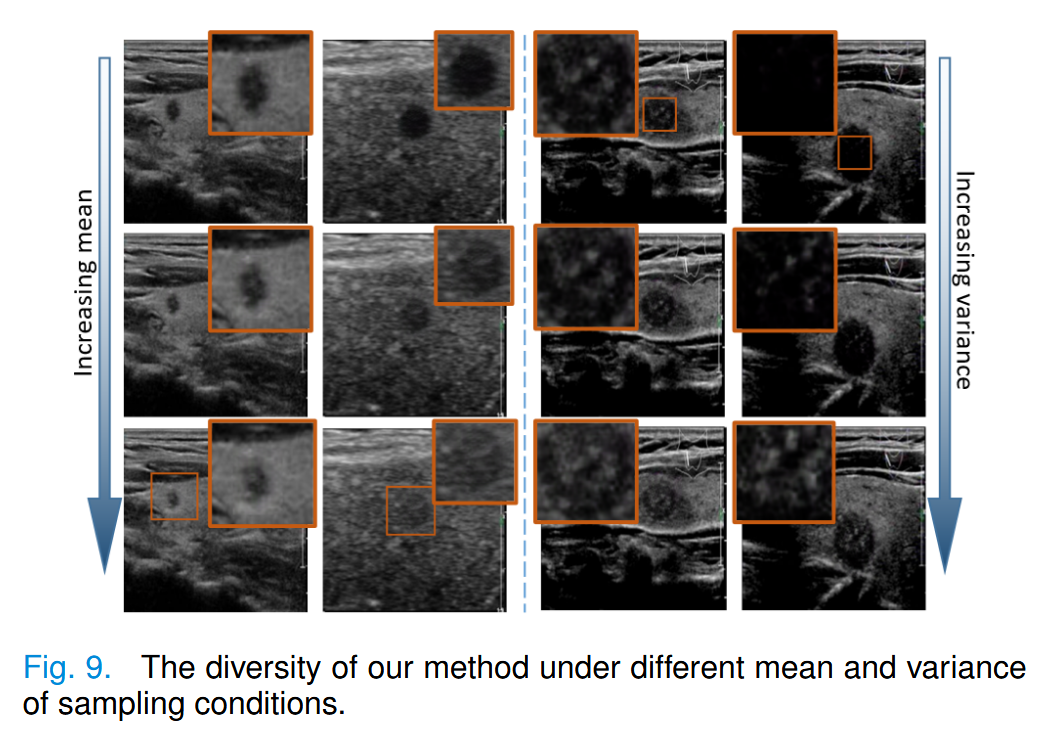

因此,我们在图9中展示了不同采样条件下的多样性。

随着采样均值的增加,生成结节的回声强度逐渐降低。

随着采样方差的增加,生成结节中的实性成分逐渐增加。

因此,我们通过采样不同均值和方差的良性和恶性结节分布,重建了多样且合理分布的新数据。